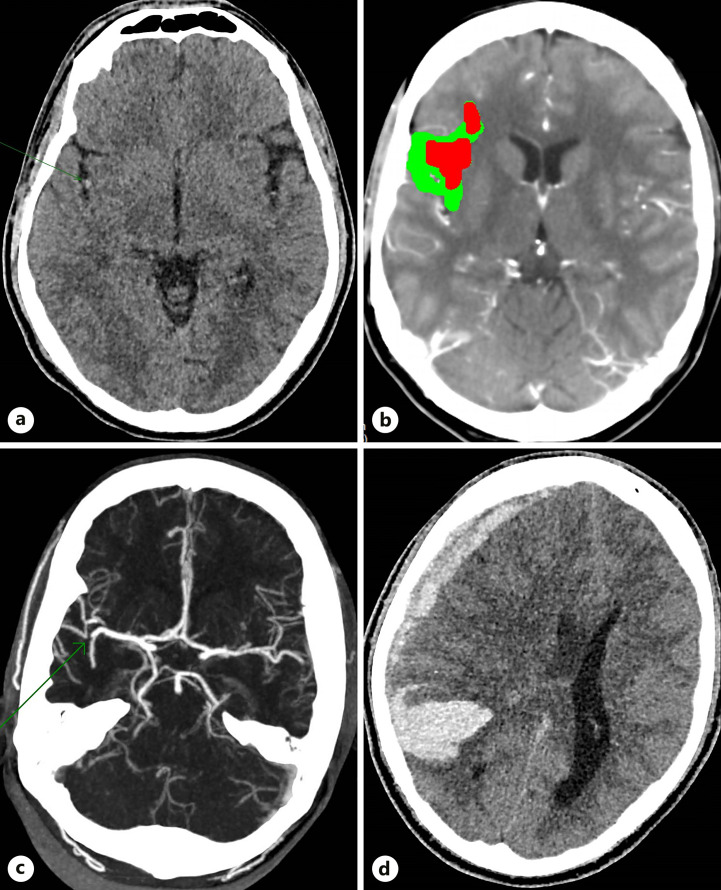

简介:黄曲霉菌是曲霉菌病的常见病因:黄曲霉菌是曲霉菌病的常见病因:病例介绍:一名居住在澳大利亚、身体健康、免疫功能正常的27岁男性发生了黄曲霉菌复合体播散性感染,并伴有纵隔和心脏受侵、上腔静脉阻塞和中风,并出现致命的出血性转变:结论:黄曲霉菌是导致免疫力低下者严重疾病的罕见但重要的病因。

Case presentation: A previously fit and well, immunocompetent 27-year-old male living in Australia developed disseminated A. flavus complex infection with mediastinal and cardiac invasion, superior vena cava obstruction and stroke, with fatal haemorrhagic transformation.